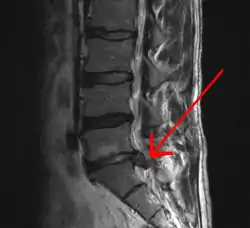

| فتق دیسک کمری در نمای امآرآی. | |

- ام آرآی: یکی از بهترین امکانات تشخیصی در فتق دیسک است. این روش میتواند ریشههای عصبی و نخاعی و بافتهای اطراف را به خوبی نشان داده و تغییرات را ثبت کند. در نمای T2 فتق دیسک نمایان میگردد.